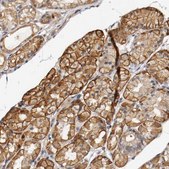

All Prestige Antibodies Powered by Atlas Antibodies are developed and validated by the Human Protein Atlas (HPA) project and as a result, are supported by the most extensive characterization in the industry.

The Human Protein Atlas project can be subdivided into three efforts: Human Tissue Atlas, Cancer Atlas, and Human Cell Atlas. The antibodies that have been generated in support of the Tissue and Cancer Atlas projects have been tested by immunohistochemistry against hundreds of normal and disease tissues and through the recent efforts of the Human Cell Atlas project, many have been characterized by immunofluorescence to map the human proteome not only at the tissue level but now at the subcellular level. These images and the collection of this vast data set can be viewed on the Human Protein Atlas (HPA) site by clicking on the Image Gallery link. We also provide Prestige Antibodies® protocols and other useful information.

• IHC tissue array of 44 normal human tissues and 20 of the most common cancer type tissues.